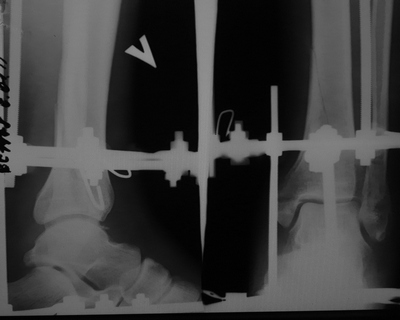

Добрый день, высылаю фото после операции

Кликните для загрузки файла DSC01505.JPG

58KB (59990 bytes)

Снимок мелковат, можно только сказать, что грубых смещений не видно. То есть картина оптимистичная.